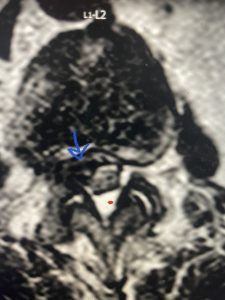

He had failed conservative treatment consisting of neurontin, physical therapy and epidural injections. He underwent revision laminectomy T12-L3 to decompress and explore prior fusion. He did have significant epidural fat encountered particularly at L1-2. The fat in epidural lipomatosis has a much more firm, globular texture. It takes a while to search within the fat, gently dissecting with a Penfield 4, to finally find the thecal sac! We encountered a large subligamentous extruded fragment lateral to the thecal sac on the right above the take off of the L2 nerve root. We removed any more residual fat at the L2-3 level and T12-L1 and decompressed the sac well. On exploration of the prior fusion it was fairly solid, but had some gaps at L2-3 fusion mass. Therefore we added a T12-L3 in situ fusion to augment those gaps and because we were at the thoracolumbar junction we extended fusion to T12. Post operatively he had relief of his leg pain.

(Figs 5a): Sagittal (a) and axial (b) T2-weighted lumbar MRI demonstrating status post lumbar decompression and insitu fusion L2-5 now well decompressed (blue dash) with development of new (red arrow) severe stenosis and with superimposed right L1-2 disc herniation (blue arrow)

(Figs 5b)